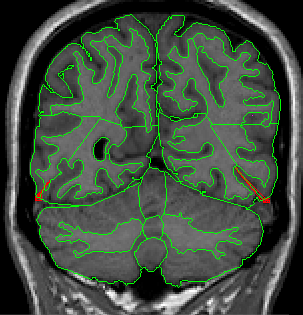

When the sulci lines that were drawn in Part 3 (here see Fig 27). are visible in the coronal as “dots,” the inferior medial section of cortex becomes occipital lobe, while the inferior lateral section remains temporal lobe. To set a boundary between the two, in the coronal view, locate the inferior lateral “corner” of the hemisphere (Fig 31). Draw a straight line from this point on the exterior to the white matter underneath it (Fig 32) Do this for both hemispheres.

Figure 31                              Figure

32

When the sulci lines that were drawn in Part 3 1.A (here see Fig 24). become visible on the coronal view (as one, long vertical line (Fig 33) the temporal lobe is no longer present.

Figure 33